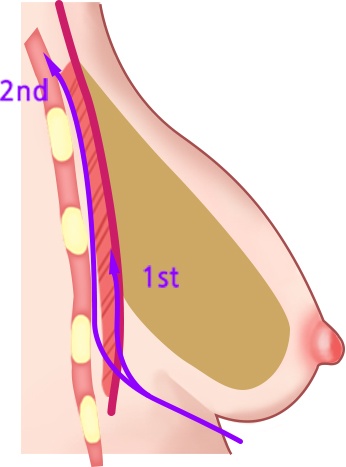

เทคนิคแบบ Dual Plane แบ่งออกเป็น 3 ประเภทใหญ่ ๆ ขึ้นอยู่กับระดับของการสร้างพื้นที่ใต้เยื่อหุ้มเซลล์

ผ่าตัดส่วนล่างของกล้ามเนื้อหน้าอกส่วนบน

เมื่อกรีดกล้ามเนื้อออก เนื่องจากแรงดึงของกล้ามเนื้อ ทำให้ส่วนบนของกล้ามเนื้อหดตัวและด้านล่างของกล้ามเนื้อจะยึดติดกับด้านล่าง

ใส่ซิลิโคนระหว่างกล้ามเนื้อที่ถูกกรีด ส่วนบนของซิลิโคนอยู่ด้านล่างของกล้ามเนื้อหน้าอก ส่วนล่างของซิลิโคนอยู่ด้านบนของกล้ามเนื้อหน้าอก

วิธีการใส่ท่อนบนของซิลิโคนลงไปใต้กล้ามเนื้อ และท่อนล่างลงไปใต้เยื่อกล้ามเนื้อ

ดึงส่วนบนของกล้ามเนื้อขึ้น

กล้ามเนื้อส่วนล่างจะยึดติดกัน

เทคนิคแบบ Dual Plane กล้ามเนื้อหดตัวลงและเคลื่อนที่ขึ้น